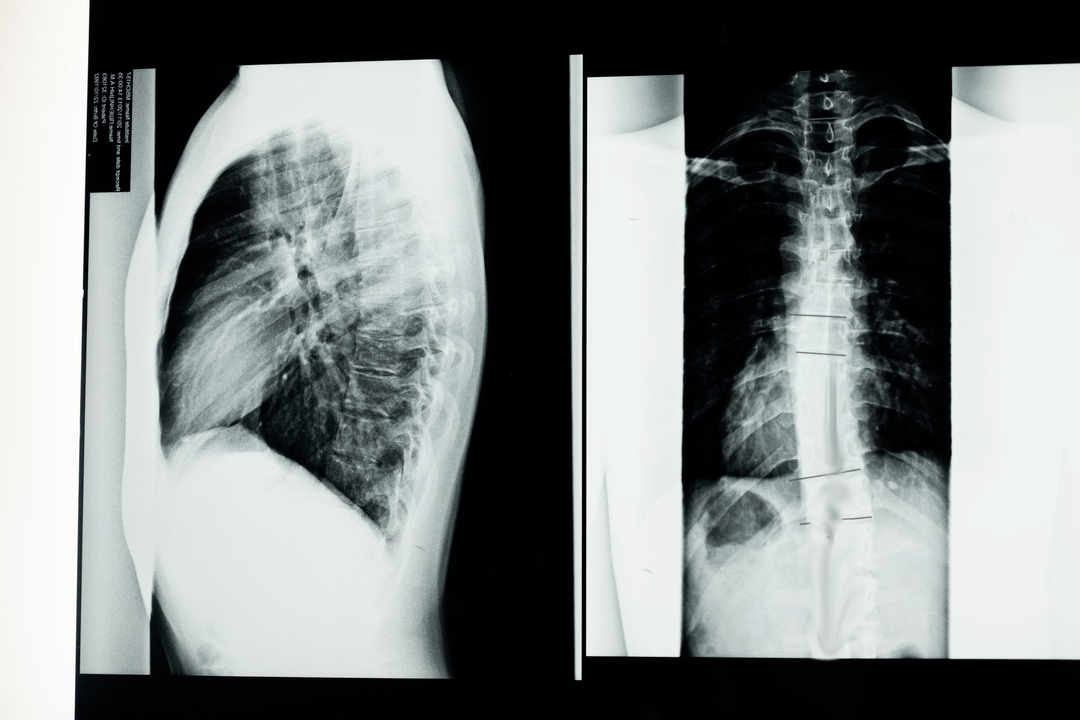

A diagnosztikai vizsgálatok megkezdése előtt a neurológus összegyűjti a beteg kórtörténetét, és gondosan megvizsgálja panaszait. Az osteochondrosisnak néhány más betegséggel közös tünetei vannak, ezért fontos a patológiák megkülönböztetése. A röntgenvizsgálatok segítenek megerősíteni az osteochondrosis diagnózisát: radiográfia, mielográfia és számítógépes tomográfia.

A felmérés röntgenfelvétele lehetővé teszi, hogy röntgenképet kapjon a gerincről vagy annak egy szakaszáról. Ily módon az orvos meghatározhatja a betegség által érintett helyet. Az egyértelműség kedvéért elmagyarázzuk, hogyan határozható meg az osteochondrosis röntgenfelvétellel: a képen a csigolyaközi porckorong szűkülete, csontkinövések (osteophyták) jelenléte vagy a gerincszegmens alakjának megváltozása látható.